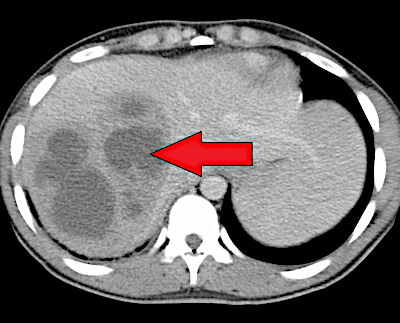

A tomografia computadorizada (acurácia 93%) revela lesões hipodensas e hipocaptantes, com halo e septos hipercaptantes. A ressonância nuclear magnética também pode ser usada, mas a CT continua o método de escolha. A colangiografia pode ser realizada para identificar cálculos do ducto biliar comum, que podem necessitar de extração endoscópica, ou estenoses e litíase intra-hepáticas, que podem exigir cirurgia definitiva ou ressecção hepática.